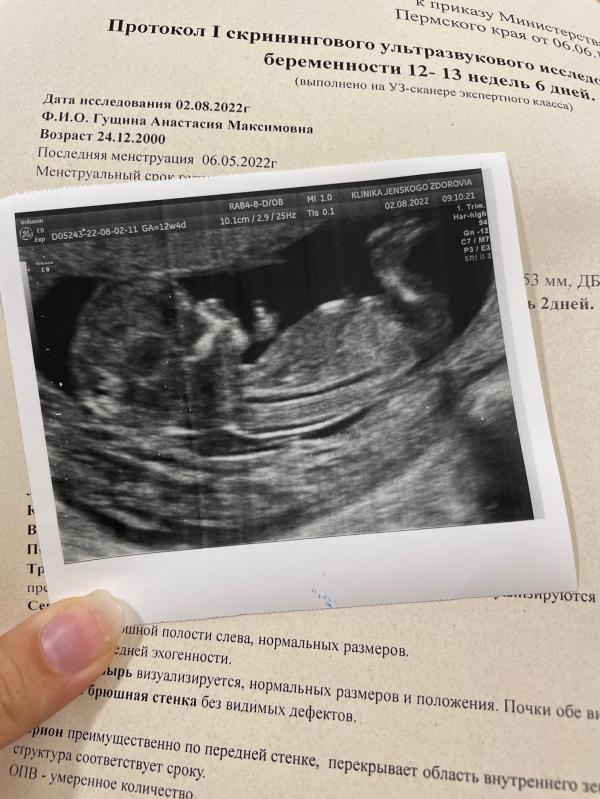

Это было лучшее бесплатное узи в моей жизни 💔 была в разных клиниках, при чем в разных городах, и платных, и в государственных, и в роддоме, но сегодняшнее прошло просто по маслу - по «телевизору» наблюдала за своим малышом, вертелся-крутился, прятался 😅 малыш развивается отлично 🙏 была на краснофлотской 31, врач Бабарыкина, отличная 👍в диагнозе низкая планцентация, но не страшно. Предположили мальчика. Все объяснили, показали, фото дали